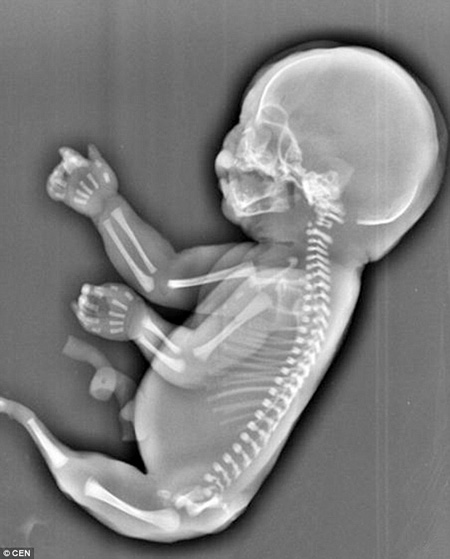

Trên thế giới, hội chứng “người cá” được coi là hiện tượng y học hiếm gặp với tỷ lệ 1/100.000 và giới y học hiện vẫn chưa có lời giải đáp chính xác. Bởi vậy, một bà mẹ người Trung Quốc mới đây đã chết lặng và buộc phải chấm dứt thai kì khi biết con mắc hội chứng này.

Bà mẹ 23 tuổi đưa ra quyết định đau đớn sau khi đến Trung tâm chăm sóc sức khỏe dành cho bà mẹ và trẻ em ở thành phố Nghi Xương, tỉnh Hồ Bắc, để khám thai. Theo Mirror, kết quả siêu âm cho thấy thai nhi không có hai chân rõ ràng mà chỉ có một chiếc đuôi. Ngoài ra, bé cũng không có bàng quang và chỉ có một lá gan nhỏ.

Các bác sĩ thông báo với mẹ bé rằng con cô bị mắc một tình trạng hiếm gặp, có tên là "Hội chứng người cá", một tinh trạng dị tật thai nhi hiếm gặp trong đó hai chân bị dính liền vào nhau, trông giống như chiếc đuôi của nàng tiên cá. Khi các bác sĩ dự tính đứa bé sau khi sinh ra sẽ chỉ có thể sống được vài giờ, Wu cân nhắc một lúc lâu và quyết định chấm dứt thai kỳ dù đã mang thai 6 tháng.

Nguyên nhân của Hội chứng người cá hiện vẫn là một bí ẩn đối với y học và tỷ lệ mắc hội chứng này là rất hiếm, chỉ trong 100.000 ca mới có một.